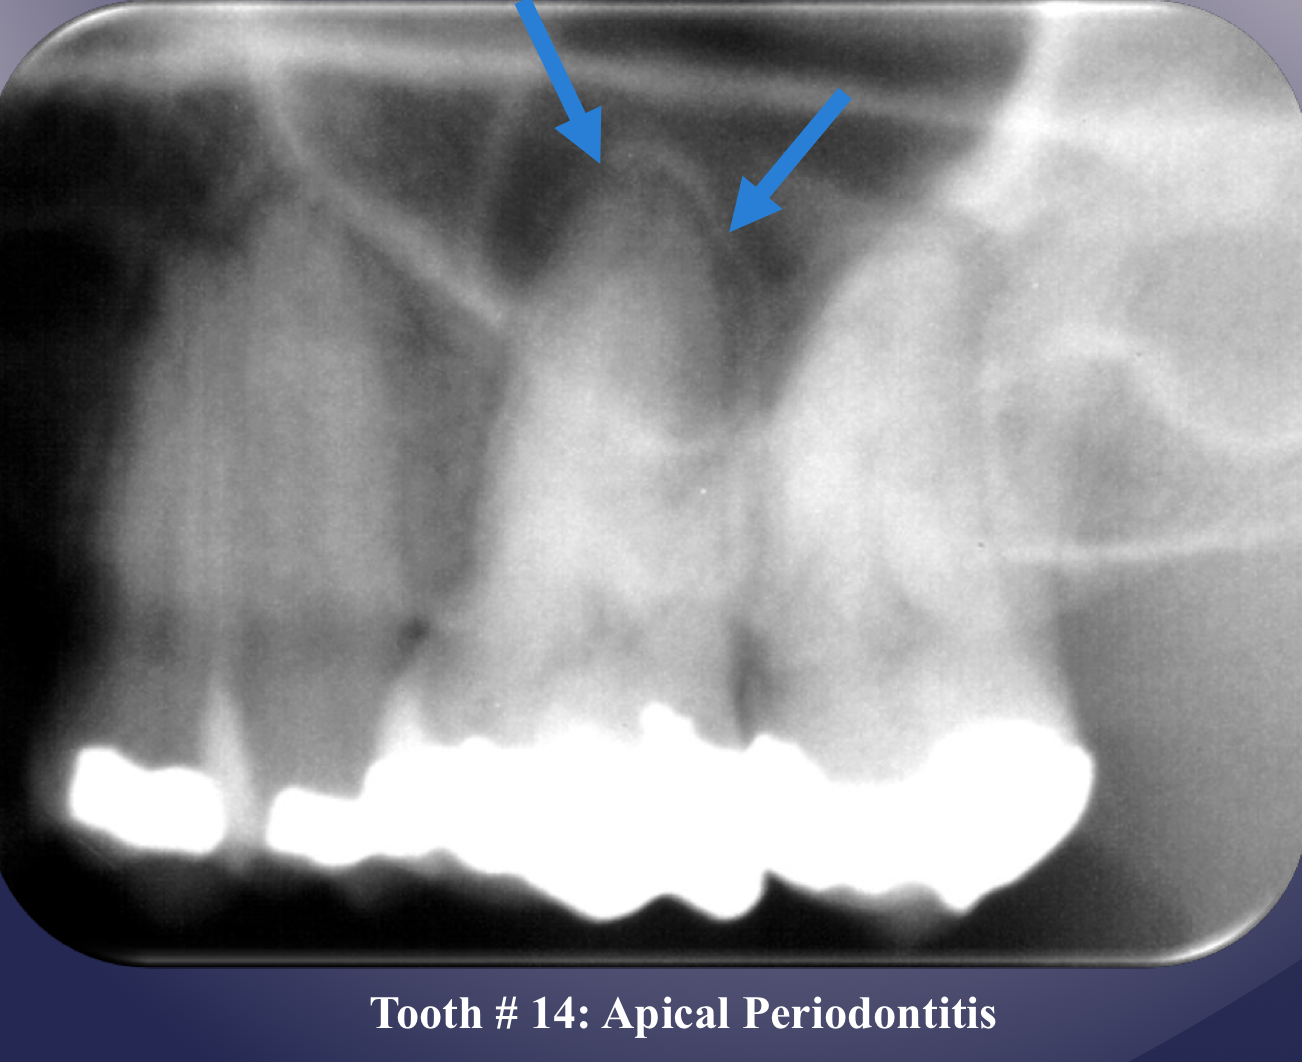

radiographic signs:

widened PDL space

loss of lamina dura

apical periodontitis

lack of continuous lamina dura, initial signÂ

apical periodontitisÂ

in maxillary M lift floor of max sinus!

elevation/displacement of floor f maxillary sinus

maxillary posterior teethÂ

periosteal bone formation in floor of maxillary sinus

periostitis and mucositisÂ

mucosal thickeningÂ